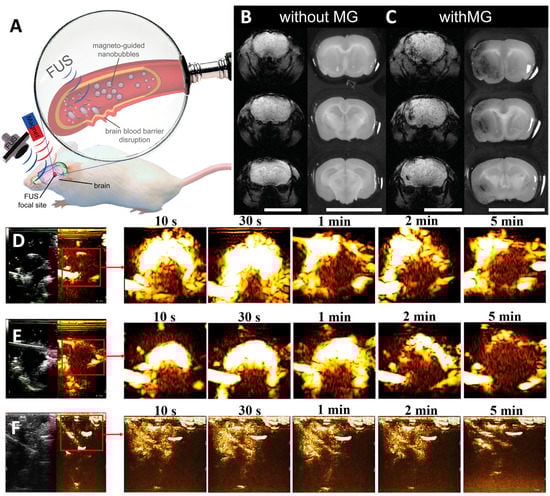

- Huang, H.Y.; Liu, H.L.; Hsu, P.H.; Chiang, C.S.; Tsai, C.H.; Chi, H.S.; Chen, S.Y.; Chen, Y.Y. A Multitheragnostic Nanobubble System to Induce Blood-Brain Barrier Disruption with Magnetically Guided Focused Ultrasound. Adv. Mater. 2015, 27, 655–661. [Google Scholar] [CrossRef]